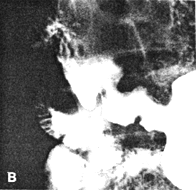

Case 29.1 C.W., 60 year old male, presented with intermittent epigastric pain and malaena. Radiographic examination showed a gastric ulcer, 2.5 cm in diameter, in the posterior wall of the upper corpus, approximately 10 cm proximal to the pylorus; the features were those of a benign ulcer. There was constant contraction (or spasticity) of the pyloric sphincteric cylinder, the contracted region being 3.0 to 4.0 cm in length (Fig. 29.1). Cyclical contraction and relaxation of the cylinder, normally occurring at a rate of 3 cylces per minute, was absent; the contraction of the cylinder "fixed" the pyloric aperture in the open or patent position. Mucosal folds in the contracted cylinder appeared normal, but their movements were restricted. A shallow, concave identation of the base of the duodenal bulb, caused by the pyloric ring, was evident. Peristaltic waves in the remainder of the stomach were normal; emptying of liquid barium appeared normal. Two weeks later a Billroth I partial gastrectomy confirmed the large, chronic gastric ulcer. No macroscopic abnormality was seen or felt in the pyloric region. Histology of the ulcer proved it to be benign; microscopic examination of the pyloric region was not carried out.

| Fig. 29.1 A-D. Case C.W. Constant contraction or spasticity of pyloric sphincteric cylinder. Cyclical activity absent. Pyloric aperture "fixed" in patent position (B-D) | |